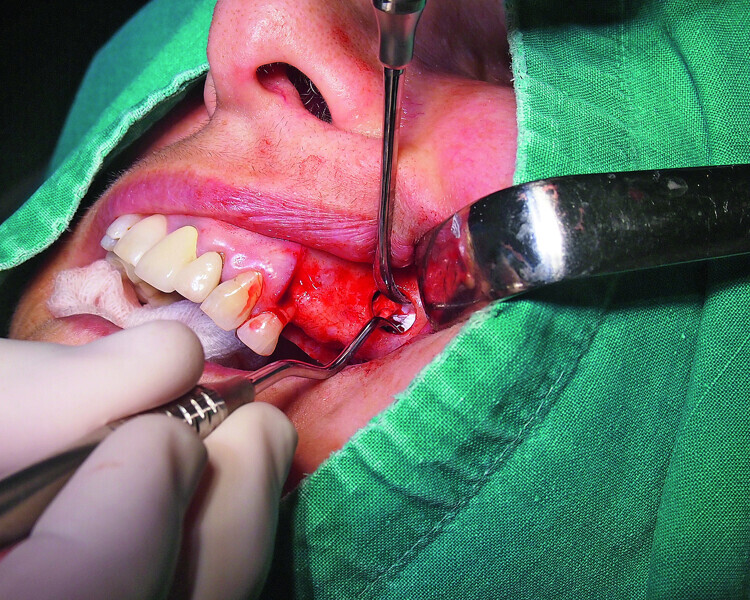

Fig. 5: Lateral window access to the maxillary sinus.